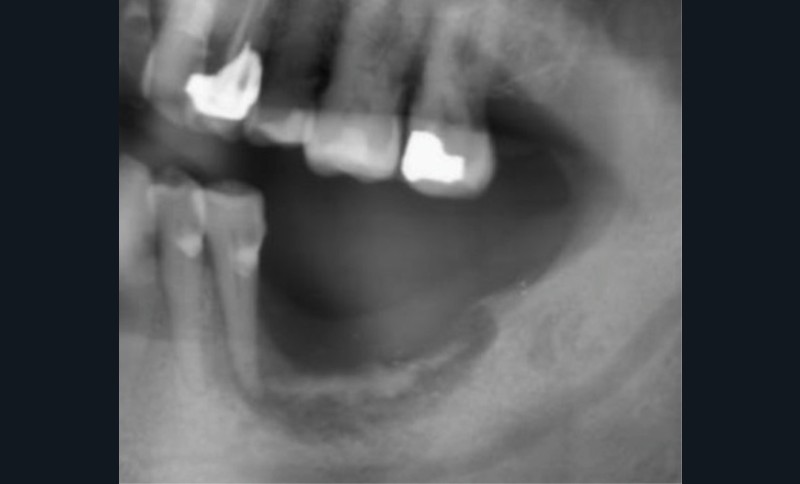

Dans le bilan avant mise en place du traitement, les recommandations, notamment de rhumatologie, indi-quent la réalisation d’un bilan dentaire et la mise en œuvre des soins nécessaires [1]. Cela a pour but d’identifier les foyers infectieux en présence et de les prendre en charge avant que le traitement ne débute, donc avant que le patient présente un risque infectieux accru (fig. 2).

L’attitude face à ces foyers infectieux, au-delà du pronostic de chaque dent, dépendra de facteurs, généraux notamment : thérapeutique mise en place (donc risque infectieux précis pour le patient), durée estimée du traitement (et donc du risque), le pronostic de la pathologie, la présence de facteurs de risque majorant le risque infectieux ou encore la compliance du patient [2].